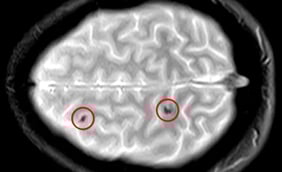

Concussions: Symptoms and Treatment

What Is a Concussion?